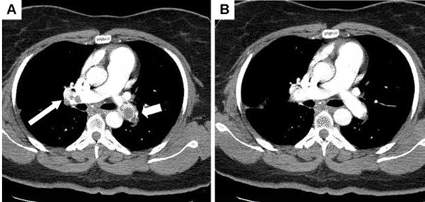

- Machine Learning Approach Enhances Liver Cancer Risk Stratification